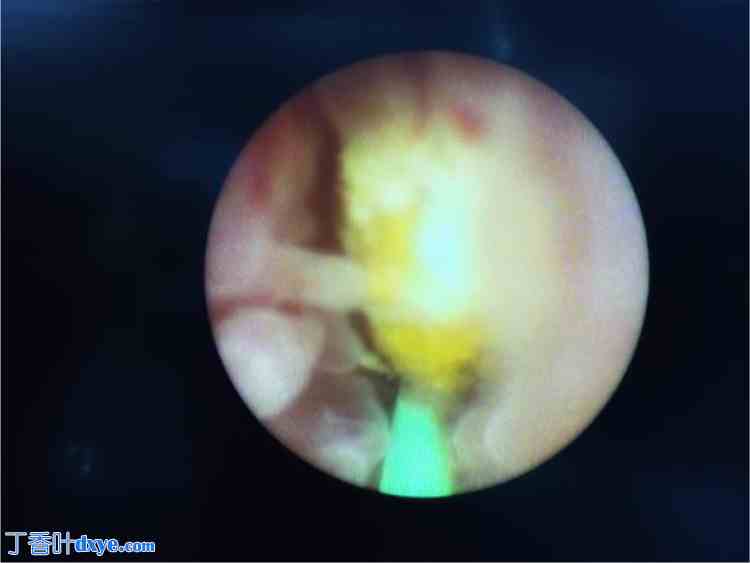

术中发现4块大小不一的结石,均已成功碎石(图5)。患者基线检查结果在1周后恢复正常。随访超声显示右侧肾积水较术前显著减少。6周后取出双J管。10天后取出肾造瘘管,后续随访影像显示尿路肿瘤已完全引流。

图5.

经输尿管碎石术用于肾结石清除。